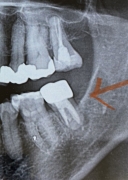

画像1

歯の根の下に黒っぽい場所(黄緑でマーキング親知らず側)があってそこから歯茎の方に膿が出ている。

CT画像からはハッキリ破折を認められない。

少し線が見える場所が6番の歯側にあるが、黄緑でマーキングした場所は根幹治療で薬が入っているところと根の治療の境目で破折ではない可能性もある とのこと。